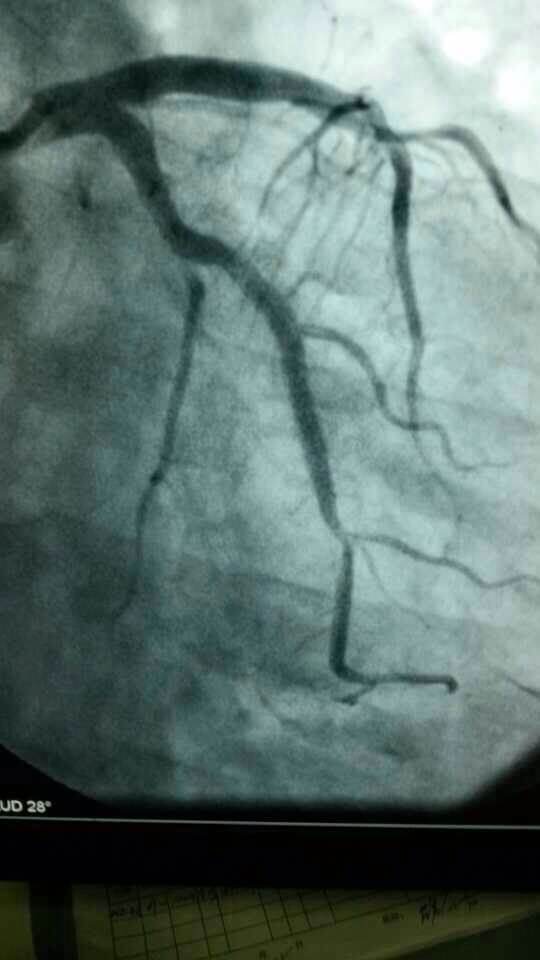

心内科医务人员在崔勇主任的带领下,蔡亚滨、林福根、雷建林、陈明辉、何晓、李仲伟等抢救团队连续奋战 8个小时成功抢救3名心梗患者。虽然工作艰辛,但接诊的三位病人都能转危为安,对医生来讲是最大的安慰。

专家提示:我国心血管病的发病率和死亡率常年居高不下,还出现明显年轻化趋势,白领、公务员等群体英年猝死的新闻屡见不鲜。在已经救治的近200例胸痛患者中,80%以上是急性冠状动脉综合征(这其中包含了心梗、不稳定心绞痛等)这类急性危险的病症,专家建议,40岁以上的人群,胸闷、胸痛突然发作,尤其是劳累后发作,或者一会儿痛一会儿不痛的要及时就诊。